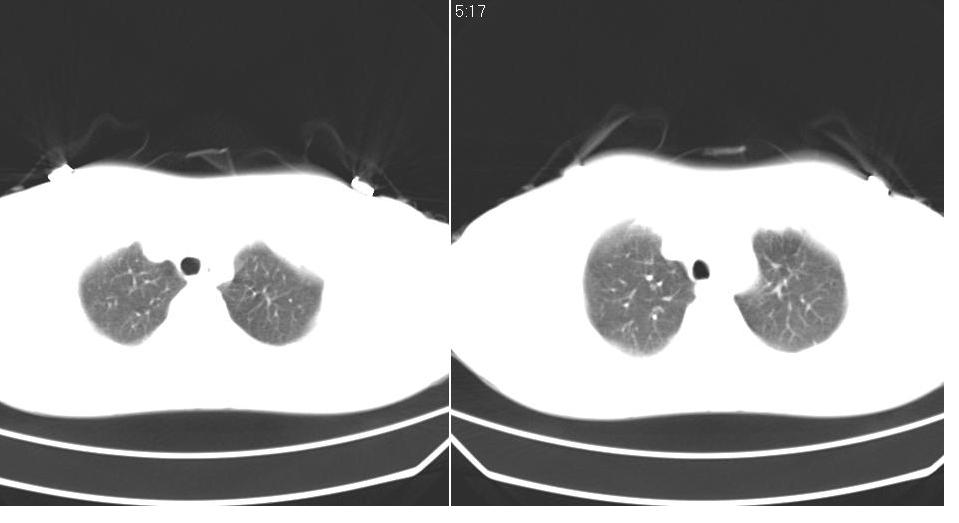

女 40岁,胸片体检发现右肺肿块,无任何症状。

下叶背段多发性小腺泡结节,考虑结核。

肺动静脉瘘可考虑,建议增强

考虑右肺下叶背段继发性肺结核。